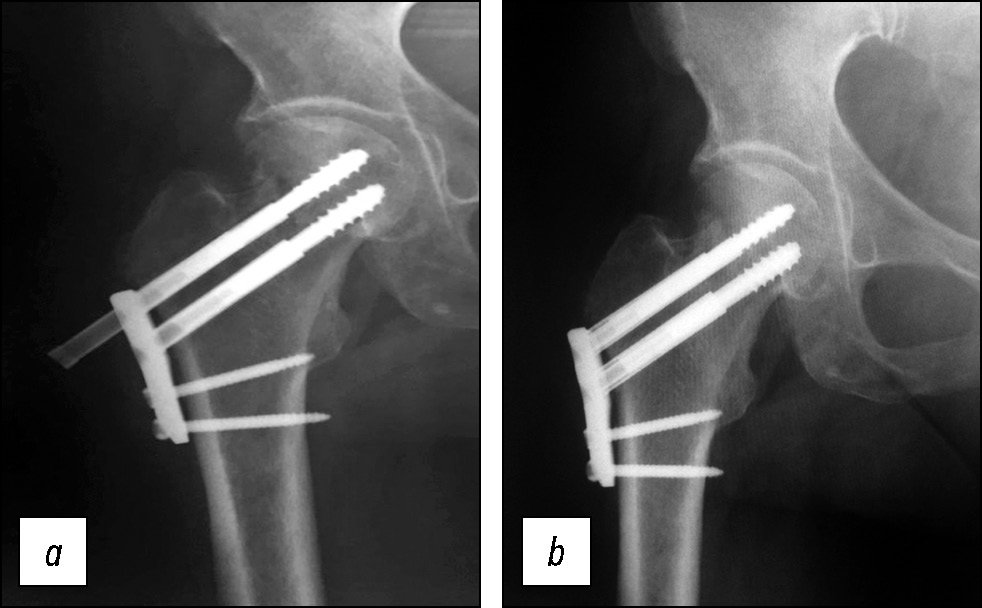

В 8 наблюдениях группы исследования (7%) при остеосинтезе с помощью ДДФ была допущена техническая ошибка при расположении пластины относительно диафиза БК, что привело к отстоянию пластины от кости (рис. 4). Послеоперационный ортопедический режим у таких пациентов не отличался от такового других больных группы исследования. При этапных контрольных осмотрах пациентов с использованием рентгенологических исследований осложнений не выявлено. Таким образом, установлено, что эта техническая ошибка не влияет на сращение перелома ШБК, не приводит к миграции фиксаторов и не увеличивает риск патологических периимплантных переломов в отдалённом послеоперационном периоде.

Рис. 4. Рентгенограмма пациента с отстоянием пластины от диафиза бедренной кости.

Fig. 4. X-ray of a patient with a plate distance from the femoral shaft.